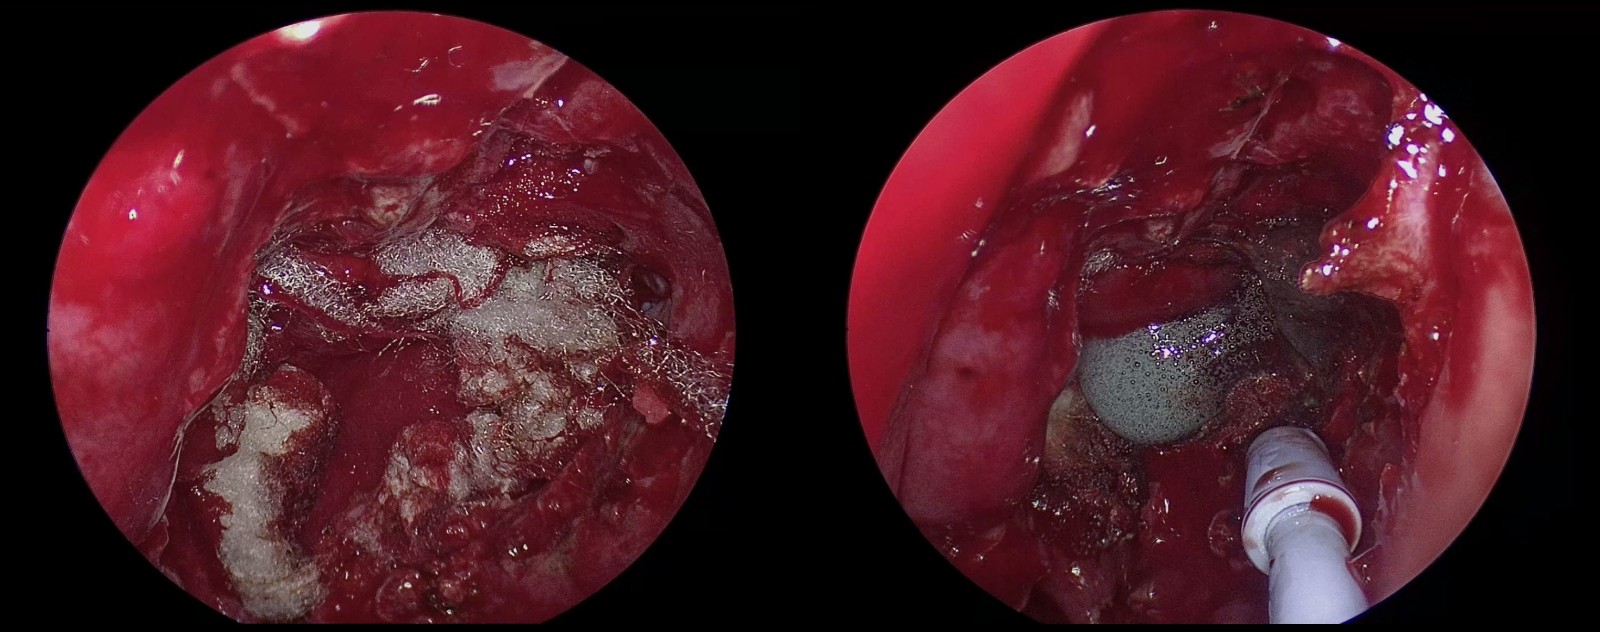

(2)切開鞍底硬膜(左)

(3)經垂體-視交叉間隙腫瘤全切(右)

(1)硬膜下放置人工硬膜,形成暫時水密封堵(左)

(2)硬膜下放置皮下脂肪,填充術區巨大缺損(右)